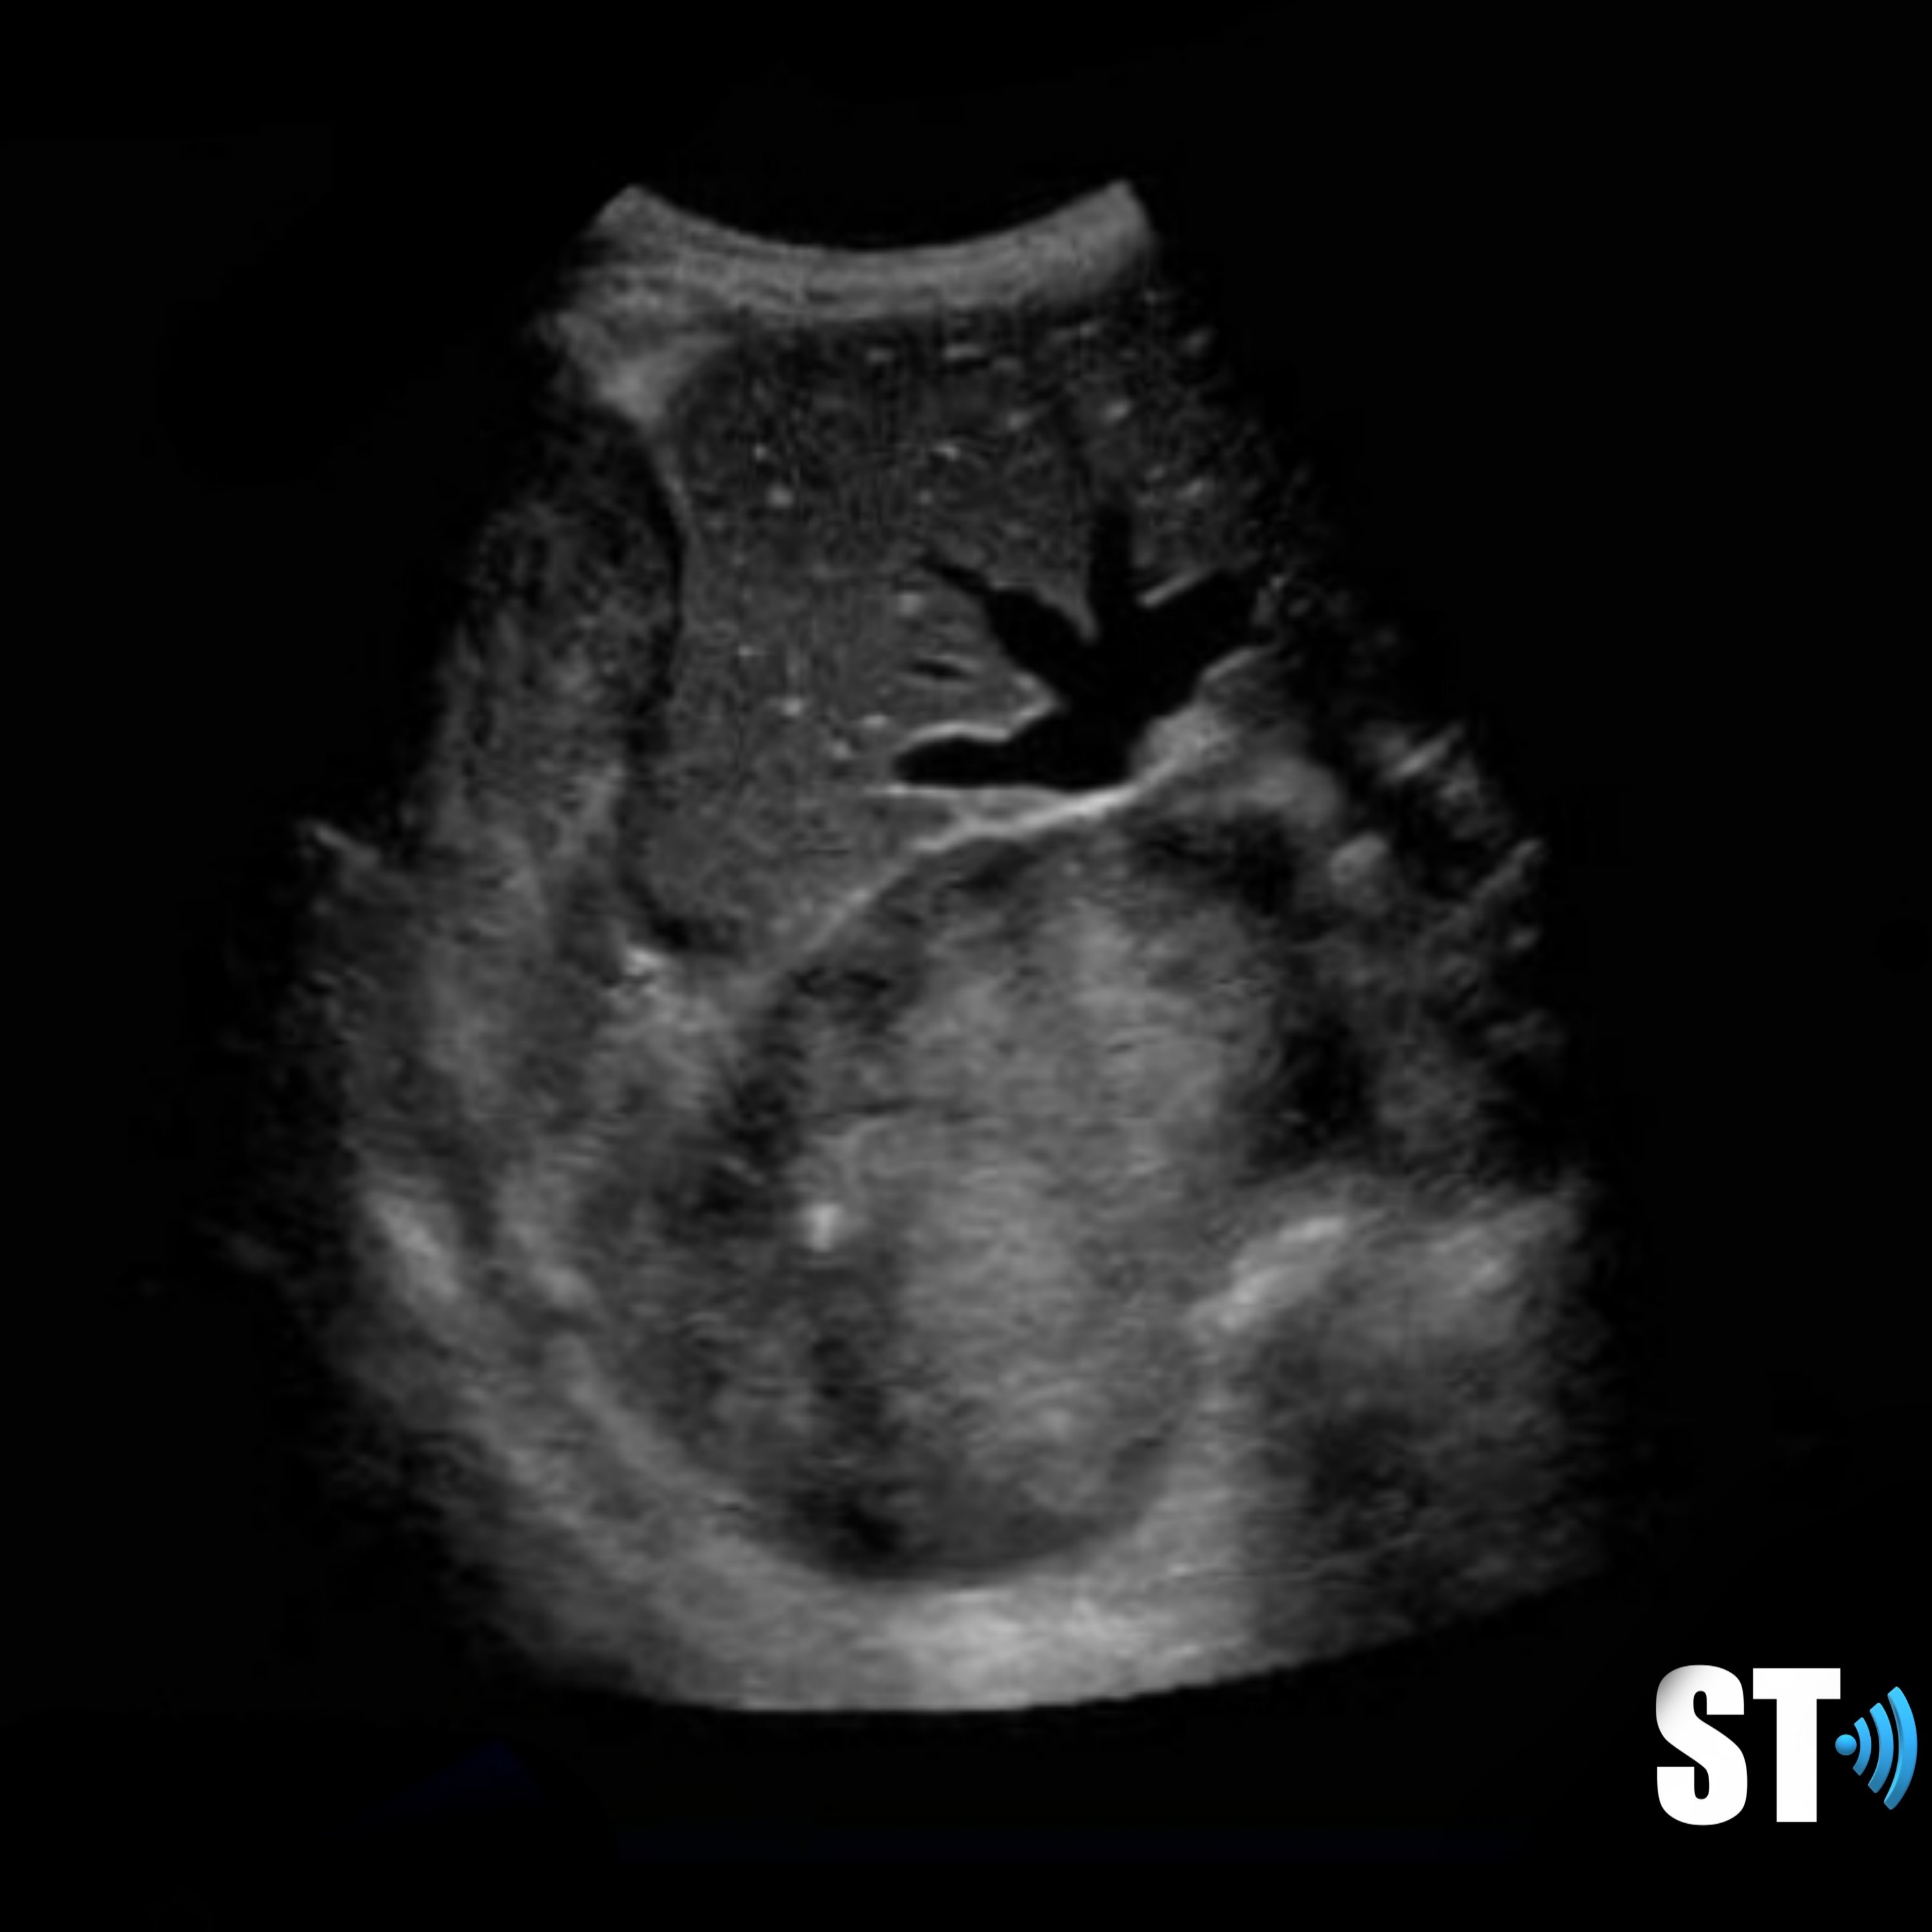

Right sided hernia with liver and hypoplastic lung

Liver and gallbladder in right chest